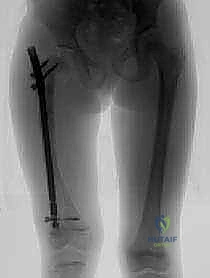

تُعد هذه العملية من أدق العمليات في جراحة عظام الأطفال، وتتطلب مهارة استثنائية كما هو الحال مع البروفيسور محمد هطيف. يتكون المسمار التلسكوبي (Fassier-Duval) من جزأين يتداخلان ببعضهما البعض (مثل التلسكوب). يتم تثبيت أحد الأطراف في أعلى العظم والطرف الآخر في أسفله. عندما ينمو العظم، ينزلق الجزء الداخلي من المسمار للخارج، مما يسمح للعظم بالنمو الطبيعي دون أن ينثني أو ينكسر.

الخطوة الرابعة: إدخال المسمار التلسكوبي

بعد تقويم العظم وجعله مستقيماً كحبات المسبحة على خيط، يتم إدخال السلك الدليلي (Guide Wire). ثم يتم إدخال الجزء الخارجي (الأنثوي) من المسمار التلسكوبي وتثبيته في الجزء العلوي من العظم (Epiphysis).

بعد ذلك، يتم إدخال الجزء الداخلي (الذكري) من المسمار عبر الجزء السفلي من العظم وتثبيته في المشاشة السفلية. هذا التصميم العبقري يضمن حماية العظم بالكامل من الداخل.

كان عمار يعاني من النوع الثالث من تخلّق العظم الناقص، مع تقوس شديد في عظمي الفخذين (بشكل حرف O) منعه من المشي تماماً، وجعله حبيس الكرسي المتحرك، مع تاريخ من 8 كسور سابقة. تم إجراء عملية بضع العظم المتعدد عبر الجلد وتركيب مسامير فاسييه-دوفال التلسكوبية في كلتا الساقين في جلسة جراحية واحدة بواسطة الدكتور هطيف. اليوم، وبعد 6 أشهر من الجراحة، يمشي عمار مستقلاً لأول مرة في حياته، ولم يتعرض لأي كسر جديد.